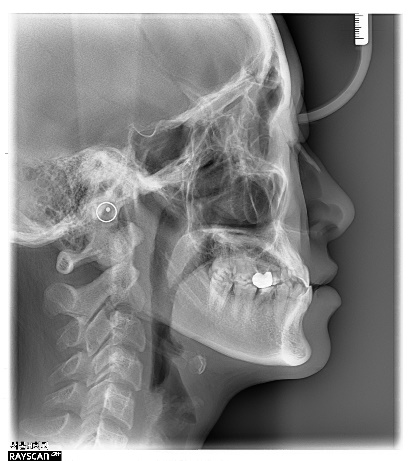

이 환자는 19세 여환으로 multiple congenitalmissing을 가지고 있으나 전치부 반대교합과 spacing의 해결만을 위해 내원하였습니다. 부분교정 시행후 상악 양측측절치 부위를 임플란트로 식립하기로결정하였습니다.

상기 환자의 경우 선천적 결손치부위인 12번과 22번의 공간은 교정으로 확보가 되어 있었으나 수술할 당시에 환자가 내원을 오랫동안 하지 않아 22번 공간에 약간의 relapse가 발생되어있는 상태였습니다.

양측 모두 처음에는 골이식없이 2.5직경의 onebody implant를 식립하였는데 22번의임플란트는 골유착 실패로 제거하게 되었습니다. 다시 마무리 교정을 한 후에 4개월 후 22번에 3.5직경의 임플란트를 골이식과 더불어 식립하였고 최종 보철물을 마무리하였습니다.

확실히 상악 전치부 동일부위에 2번의 수술을 진행하는 경우는 harmonic gingival line을 맞추는 것은 쉬운일이 아니라고 생각됩니다.